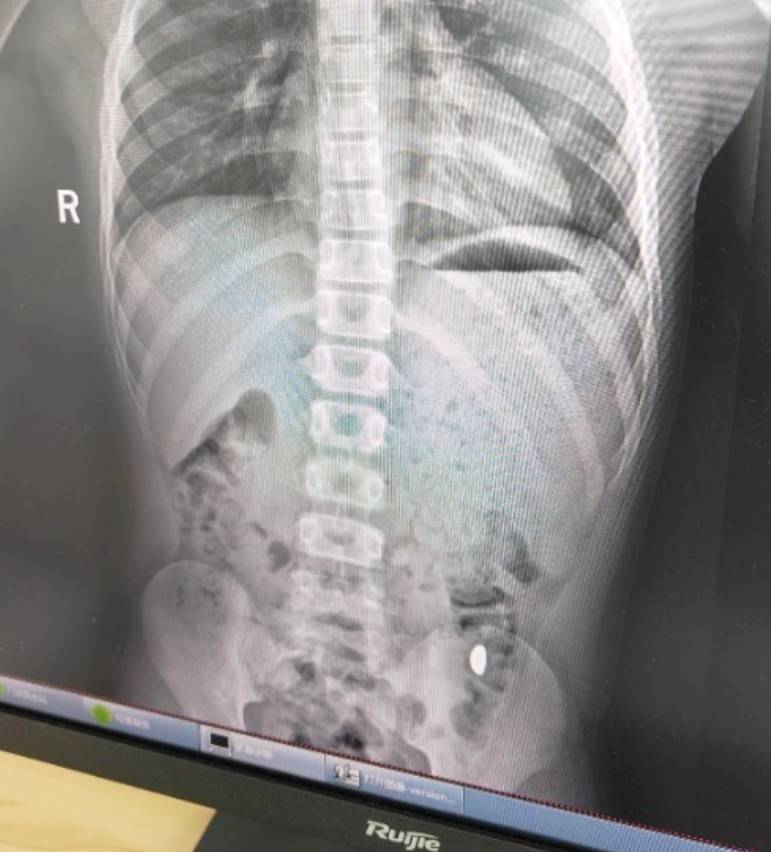

右下加亮点为金豆电商资讯平台。